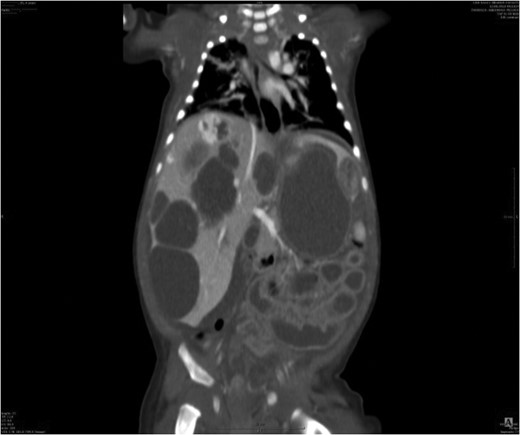

Abdominal ultrasound showed enlarged liver with multi nodular hypo-hyperechogenic hepatic lesions with complete distortion of hepatic vasculature. Computed tomography (CT) scan with contrast injection showed co-existing multifocal hepatic solid and macro-cystic lesions with no hepatic calcifications (Fig. 1).

Large cystic lesions with internal septation associated with heterogeneous small solid lesions with arterial enhancement.